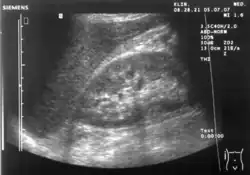

Ultrasound of liver (left side of the image) and right kidney (right side of the image) and Morison's pouch, not containing fluid -